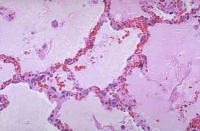

肺表面苍白,含水量增多,切面有大量液体渗出。显微镜下观察,可将其分为间质期,肺泡壁期和肺泡期。

间质期是肺水肿的最早表现,液体局限在肺泡外血管和传导气道周围的疏松结缔组织中,支气管、血管周围腔隙和叶间隔增宽,淋巴管扩张。液体进一步潴留时,进入肺泡壁期。液体蓄积在厚的肺泡毛细血管膜一侧,肺泡壁进行性增厚。发展到肺泡期时,可见充满液体的肺泡壁丧失了环形结构,出现褶皱。无论是微血管内压力增高还是通透性增加引起的肺水肿,肺泡腔内液体的蛋白均与肺间质内相同,提示表面活性物质破坏,而且上皮丧失了滤网能力。